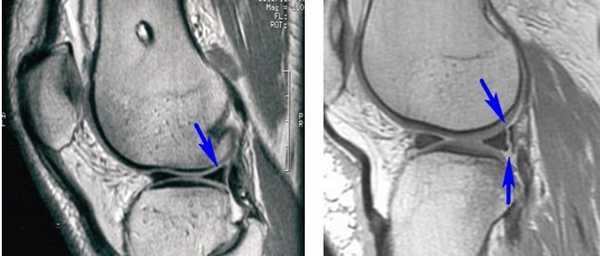

Длительность хирургического вмешательства обычно зависит от степени повреждения мениска. В среднем артроскопия длится 60 минут. В сложных случаях она может продолжаться 1,5-2 часа. На МРТ справа — разрыв заднего рога мениска, слева — здоровый мениск.